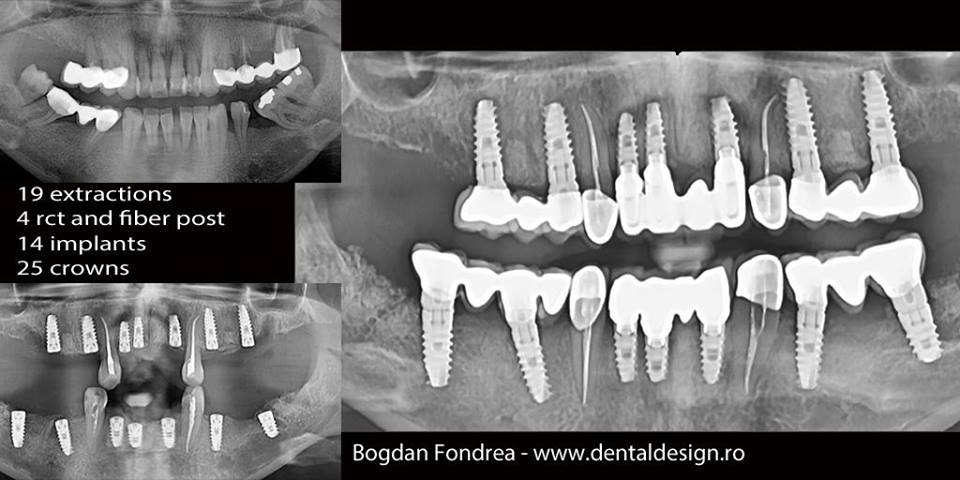

Cazul 1 – se poate pune un diagnostic și se poate face un plan de tratament general, se verifică tratamentele efectuate și rezultatul obținut. Astfel există certitudinea unui act medical corect.